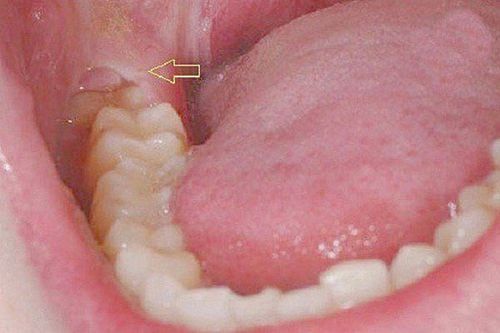

- The Pain of Impaction and Infection: This is a different beast altogether. It occurs when a tooth fails to erupt fully (becoming impacted), creating a flap of gum tissue that traps food debris and bacteria. This leads to a condition called pericoronitis—an infection characterized by sharp, severe pain, intense redness, swelling, and often a terrible taste in your mouth or even pus. This pain is acute, intense, and a clear sign of a problem that won’t resolve on its own.